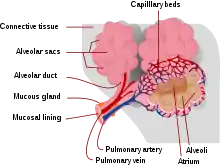

Respiratory zone

The conducting zone of the respiratory tract ends at the terminal bronchioles when they branch into the respiratory bronchioles. This marks the beginning of the terminal respiratory unit called the acinus which includes the respiratory bronchioles, the alveolar ducts, alveolar sacs, and alveoli.[27] An acinus measures up to 10 mm in diameter.[28] A primary pulmonary lobule is the part of the lung distal to the respiratory bronchiole.[29] Thus, it includes the alveolar ducts, sacs, and alveoli but not the respiratory bronchioles.[30]

The unit described as the secondary pulmonary lobule is the lobule most referred to as the pulmonary lobule or respiratory lobule.[25]: 489 [31] This lobule is a discrete unit that is the smallest component of the lung that can be seen without aid.[29] The secondary pulmonary lobule is likely to be made up of between 30 and 50 primary lobules.[30] The lobule is supplied by a terminal bronchiole that branches into respiratory bronchioles. The respiratory bronchioles supply the alveoli in each acinus and is accompanied by a pulmonary artery branch. Each lobule is enclosed by an interlobular septa. Each acinus is incompletely separated by an interlobular septa.[28]

The respiratory bronchiole gives rise to the alveolar ducts that lead to the alveolar sacs, which contain two or more alveoli.[20] The walls of the alveoli are extremely thin allowing a fast rate of diffusion. The alveoli have interconnecting small air passages in their walls known as the pores of Kohn.[20]